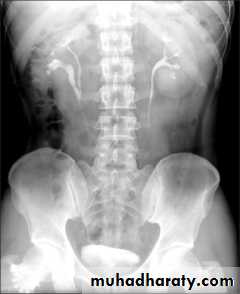

Ectopia vesica :

bladder located at low position & plain x-ray shows separation of symphysis pubis .